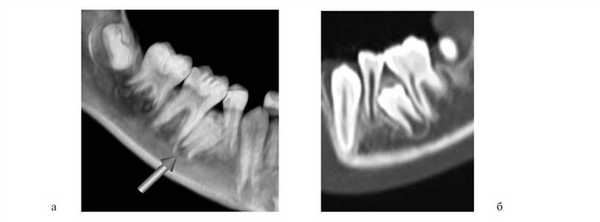

При преждевременном удалении вторых молочных моляров зубы, окружающие дефект, могут наклонно-вращательно смещаться язычно и в сторону дефекта. Может происходить сокращение зубной дуги и блокирование вторых премоляров (рис. 12). Рисунок 12. Блокирование вторых премоляров (пациент И.М.).

Такое сокращение зубной дуги является результатом мышечно-артикуляционного баланса. Размеры челюсти при этом могут быть достаточными, а зачаток второго премоляра правильно располагаться в альвеолярном отростке. Несмотря на значительное сокращение зубной дуги, аппаратурное ортодонтическое создание пространства и нормализация положения зубов в подобных случаях не являются сложной задачей. Сами зубы также адаптируются к ограниченному пространству для формирования. Верхушки корней зубов искривляются: чем существеннее недостаток пространства, тем большая часть корня зуба искривлена. Также в подобных случаях может наблюдаться уменьшение длины корней зубов (рис. 13). Рисунок 13. Искривление корней зубов вследствие уменьшенного размера челюстей. а — пациент З.Д.; б — пациент Л.А.